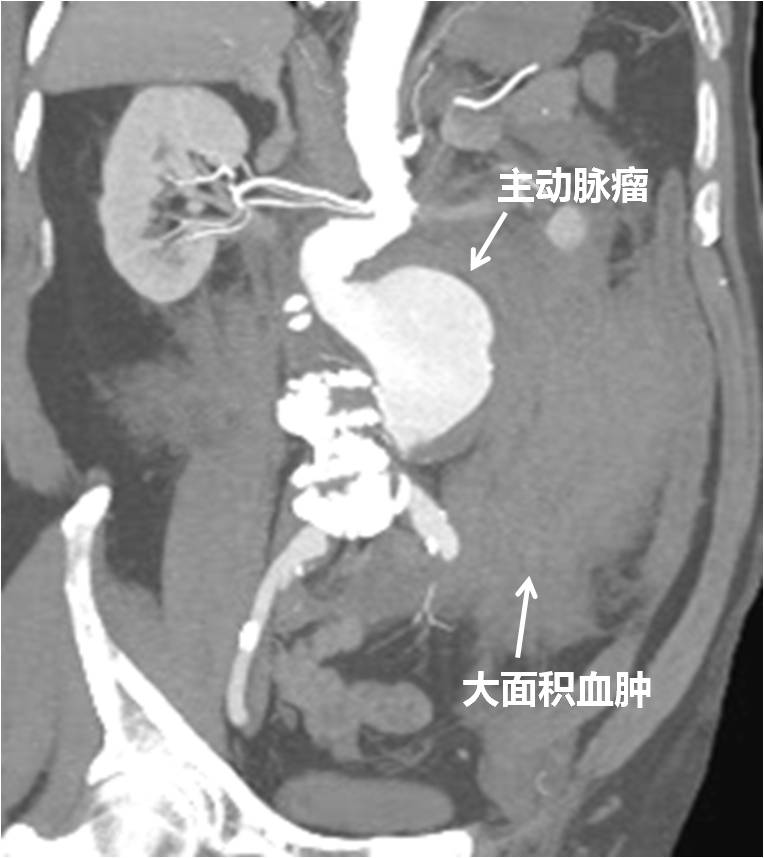

2018年2月25日,是春节假期结束后的第一个休息日,当人们仍沉浸在新春的祥和气氛中时,76岁的李大爷却在当天凌晨2点多钟,突发左侧腰背部剧烈疼痛令他无法忍受,半夜来到北医三院急诊就诊。泌尿外科急诊值班医师接诊后,察觉患者病情不简单,紧急请介入血管外科会诊。介入血管外科韩金涛副主任医师迅速赶到,完善全主动脉CTA检查后发现,患者的病因是介入血管外科疾病里最为凶险的病种之一的破裂性腹主动脉瘤。(如图1-2)

图1

图2